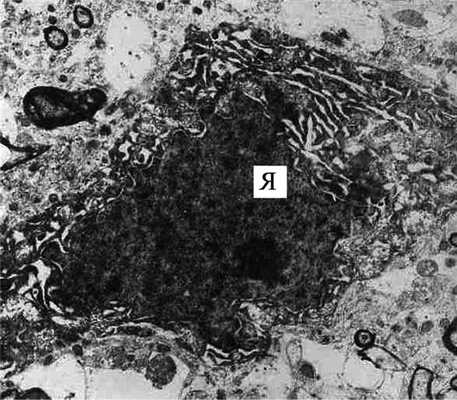

Рис. 4. СМК крысы после ДС. ЭР - свободные эритроциты в ткани мозга, окруженные миелиновыми волокнами (МВ) с выраженной миелино- и аксонопатией. Справа - нейрон с ядром (Я) в состоянии кариорексиса. Ув. 8000.